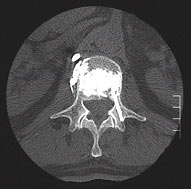

Der Patient befindet sich in Bauchlage, es werden dann zwei spezielle Kanülen ohne Hautschnitt durch den Wirbelbogen (transpedikulär) in den Wirbelkörper eingebracht.

Abb.1oben

Schematische Darstellung des Einbringens der Punktionskanüle in den Wirbelkörper durch den Wirbelbogen (transpedikulär)